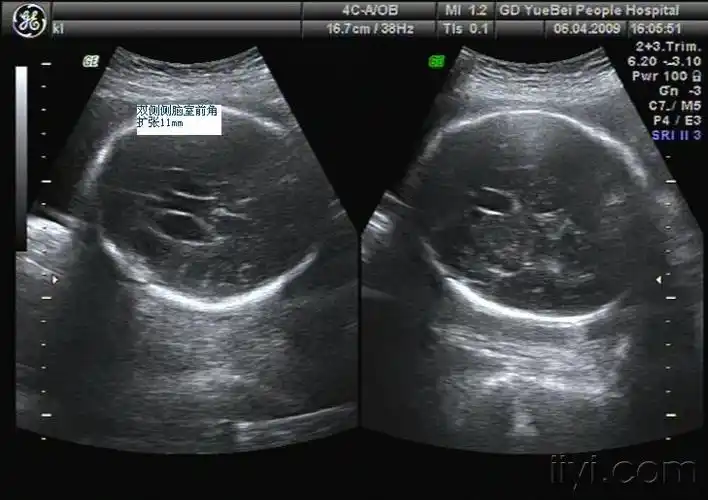

比较少见的胎儿侧脑室前角积液